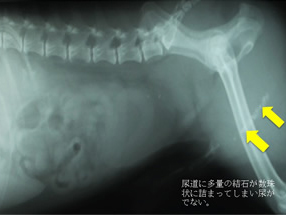

結石破砕システムを使うと尿道に詰まった石を砕き回収することができる。 経尿道的結石破砕術:TULと体外衝撃波破石術:ESWLの2つの治療法があります。当院で行っているのはTULになります。ESWLは小型犬には適応が難しく動物医療では行っているところはありません。TULも当院が日本で初めておこなう高度先進医療です。

尿道結石がスタックされていて膀胱内に押し込むこともできない。押し込んでも何度も落ちてきて尿道に詰まってしまうことがある。

他院からの紹介:結石が詰まってチョロチョロしか尿が でずカテーテルも通らない。

結石破砕を依頼された。左が破砕前、陰茎骨に結石が詰まっている。

右は破砕後。破砕が可能だったので尿道切開をせずに2時間後に帰宅した。